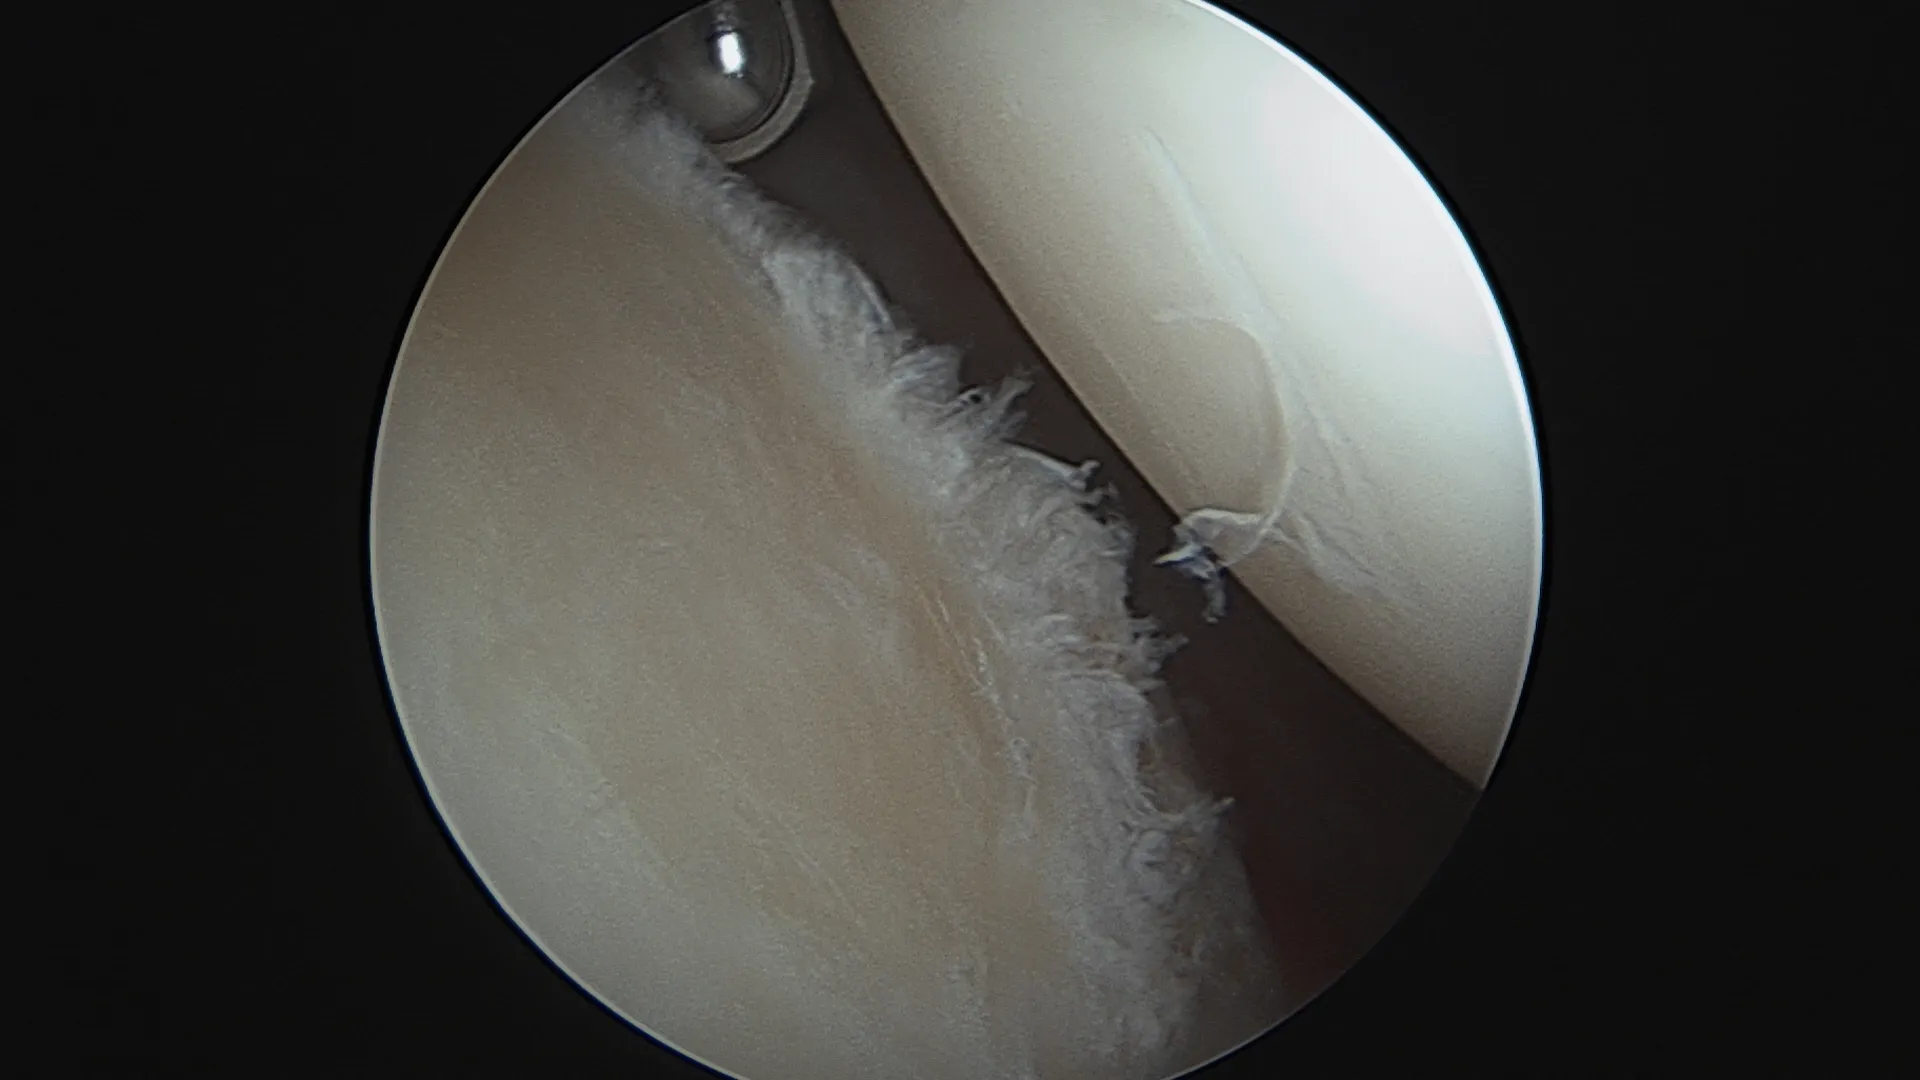

La lésion de bankart sous arthroscopie

Les lésions labrales:

Le labrum est un fibrocartilage qui circonscrit la surface osseuse glénoïdienne. Il a pour rôle d'augmenter la stabilité de l'articulation de l'épaule et d'empêcher la tête humérale de se déplacer hors de la cavité glénoïdienne. Lors d'un épisode de luxation de l'épaule le labrum peut se détacher de la surface osseuse : cette lésion est appelée une lésion de Bankart.

Dans certains cas elle peut également cicatriser, cela dépend de l'étendue de la lésion, de l'âge du patient et du traitement médical (immobilisation) qui a été proposé.

La cicatrisation du labrum survient surtout lorsqu'il s'agit d'un premier épisode de luxation.

Ces lésions sont réparées lorsqu'une chirurgie arthroscopique est proposée.